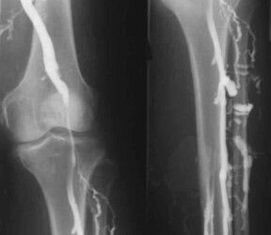

The most common instrumental diagnostic method is the use of ultrasound examination of the venous vessels of the legs.This technique allows you to visualize the vascular system and identify the degree of evolution of the pathological process.

- Phlebography.

- Photoplethysmography.

The use of venous occlusion plethysmography makes it possible to determine the blood volume in the veins of the lower limbs.